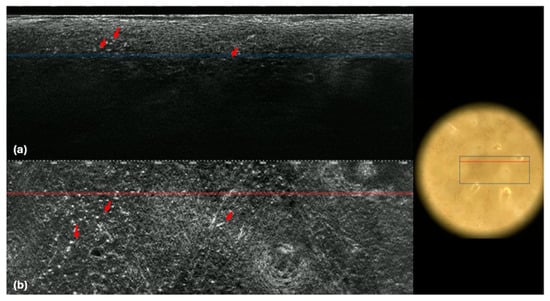

| Folliculotropism Hyper-reflective round cells 5 to 10 μm in diameter around hair follicles |